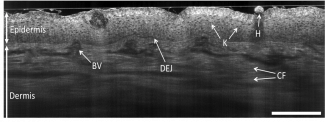

Tomographie par cohérence optique

Image d'OCT de la peau

Nous développons de nouvelles techniques d'imagerie interférométrique, l'OCT plein champ et l'OCT confocale ligne pour répondre à des besoins spécifiques dans le domaine biomédical. Une partie de ces activités de recherche est valorisée par la startup DAMAE Medical pour applications en dermatologie. (Responsable : Arnaud Dubois)